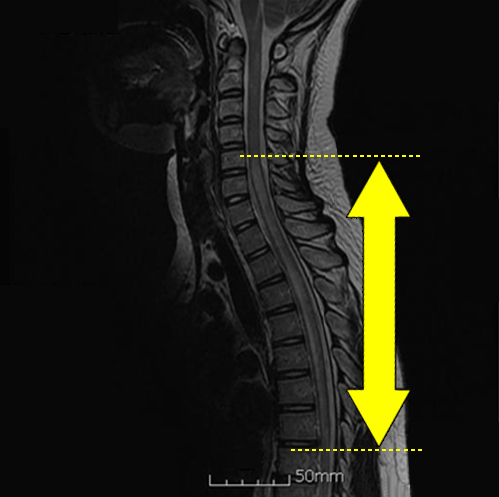

Clinical characteristics, prognosis, and seropositivity to the anti-aquaporin-4 antibody in Korean patients with longitudinally extensive transverse myelitis

발표지

-

2010.06